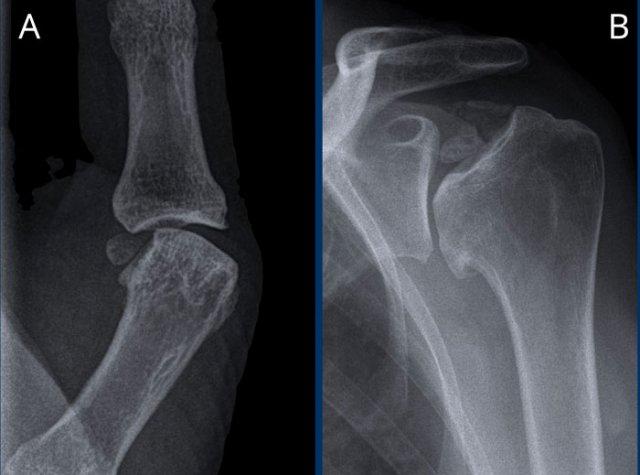

Hình ảnh

A. Vôi hóa mô mềm tại chóp xoay. Bệnh nhân được tiêm dưới mỏm cùng vai để giảm triệu chứng.

B. Sau tiêm corticosteroid, xuất hiện mất sụn khớp nặng tại khớp ổ chảo-cánh tay và phá hủy xương đầu trên xương cánh tay. Đây là hậu quả của viêm khớp nhiễm khuẩn, một biến chứng hiếm gặp của tiêm khớp.

Dấu hiệu rìu so với hoại tử vô mạch

Dấu hiệu rìu khác với biến dạng thấy trong hoại tử vô mạch, trong đó có hiện tượng xẹp tiến triển của bề mặt khớp chỏm xương cánh tay.

Vai Milwaukee

Hội chứng vai Milwaukee là một bệnh lý khớp vai hiếm gặp có thể bắt chước hình ảnh vai hình rìu.

Bệnh đặc trưng bởi đứt gân chóp xoay, tràn dịch khớp và bao hoạt dịch lớn kèm lắng đọng tinh thể hydroxyapatite dẫn đến phá hủy nhanh chóng khớp ổ chảo-cánh tay.

Phá hủy nặng nề chỏm xương cánh tay với di lệch lên trên và bào mòn mỏm cùng vai, cho thấy đứt hoàn toàn gân chóp xoay.

Trong hội chứng vai Milwaukee, triệu chứng lâm sàng thường nhẹ hơn nhiều so với mức độ tổn thương trên hình ảnh.

Trong trường hợp này, không có nỗ lực chẩn đoán tinh thể canxi hydroxyapatite trong màng hoạt dịch.

Dựa trên các dấu hiệu lâm sàng và X-quang, hội chứng vai Milwaukee đã được chẩn đoán.